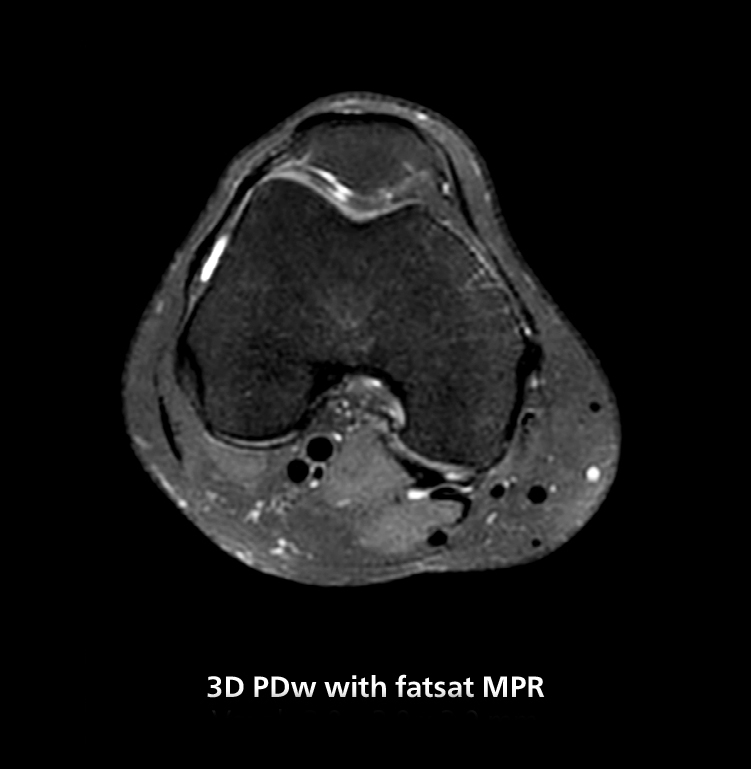

3D knee imaging

The isotropic high resolution 3D sequence in this MRI case allows for reformatting to obtain other orientations with high quality. Acquired on the MR 5300 system.

3D knee imaging

The isotropic high resolution 3D sequence in this MRI case allows for reformatting to obtain other orientations with high quality. Acquired on the MR 5300 system.

“We have more speed in 3D sequences,” Dr. Gellée states. “With Compressed SENSE, we can replace two or three 2D scans withone high-quality 3D scan. High quality additional orientations are then obtained by post-processing of the 3D data set, thus saving scanning time.”